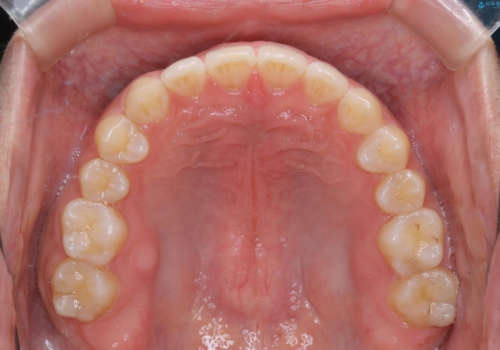

- 上のすきっ歯が気になるとご相談にいらした方です。上下顎ともにスペースがあったため、インビザラインFULLにて見た目と噛み合わせの改善も同時に行いました。

元々は上前歯のみの部分矯正をご希望されていましたが、下の歯もスペースがあり、噛み合わせ的にも上のみの部分治療は難しいことをお話ししました。前歯のみの部分矯正を行った場合、前歯の隙間だけが閉じて奥歯が噛めなくなってしまう場合もあります。インビザラインFULLにて治療することで、噛み合わせと見た目を同時に改善させることができ、大変喜んでいただけました。